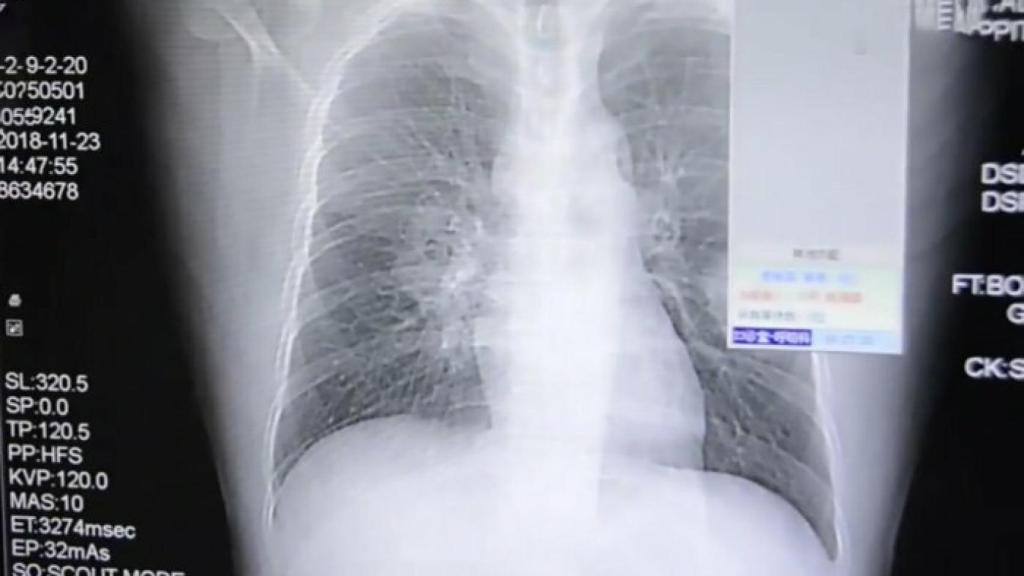

Radiografía del paciente.

Peng acudió entonces a su hospital de referencia de Zhangzhou, en la provincia china de Fujian. Inicialmente se sospechó una neumonía, pero los síntomas continuaron sin mejoría alguna pese al tratamiento por lo que se continuó con las pruebas y exámenes médicos buscando algún diagnóstico alternativo.

Finalmente, se llegó a la conclusión de que se trataba de una infección micótica grave en los pulmones: hongos en sus vías respiratorias. Se trata de un tipo de infección que si bien no es imposible en un paciente sano, es más típico encontrarla en individuos con enfermedades "debilitantes" previas como los pacientes con SIDA o con patologías crónicas como la diabetes mellitus.